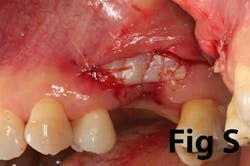

Case No. 1